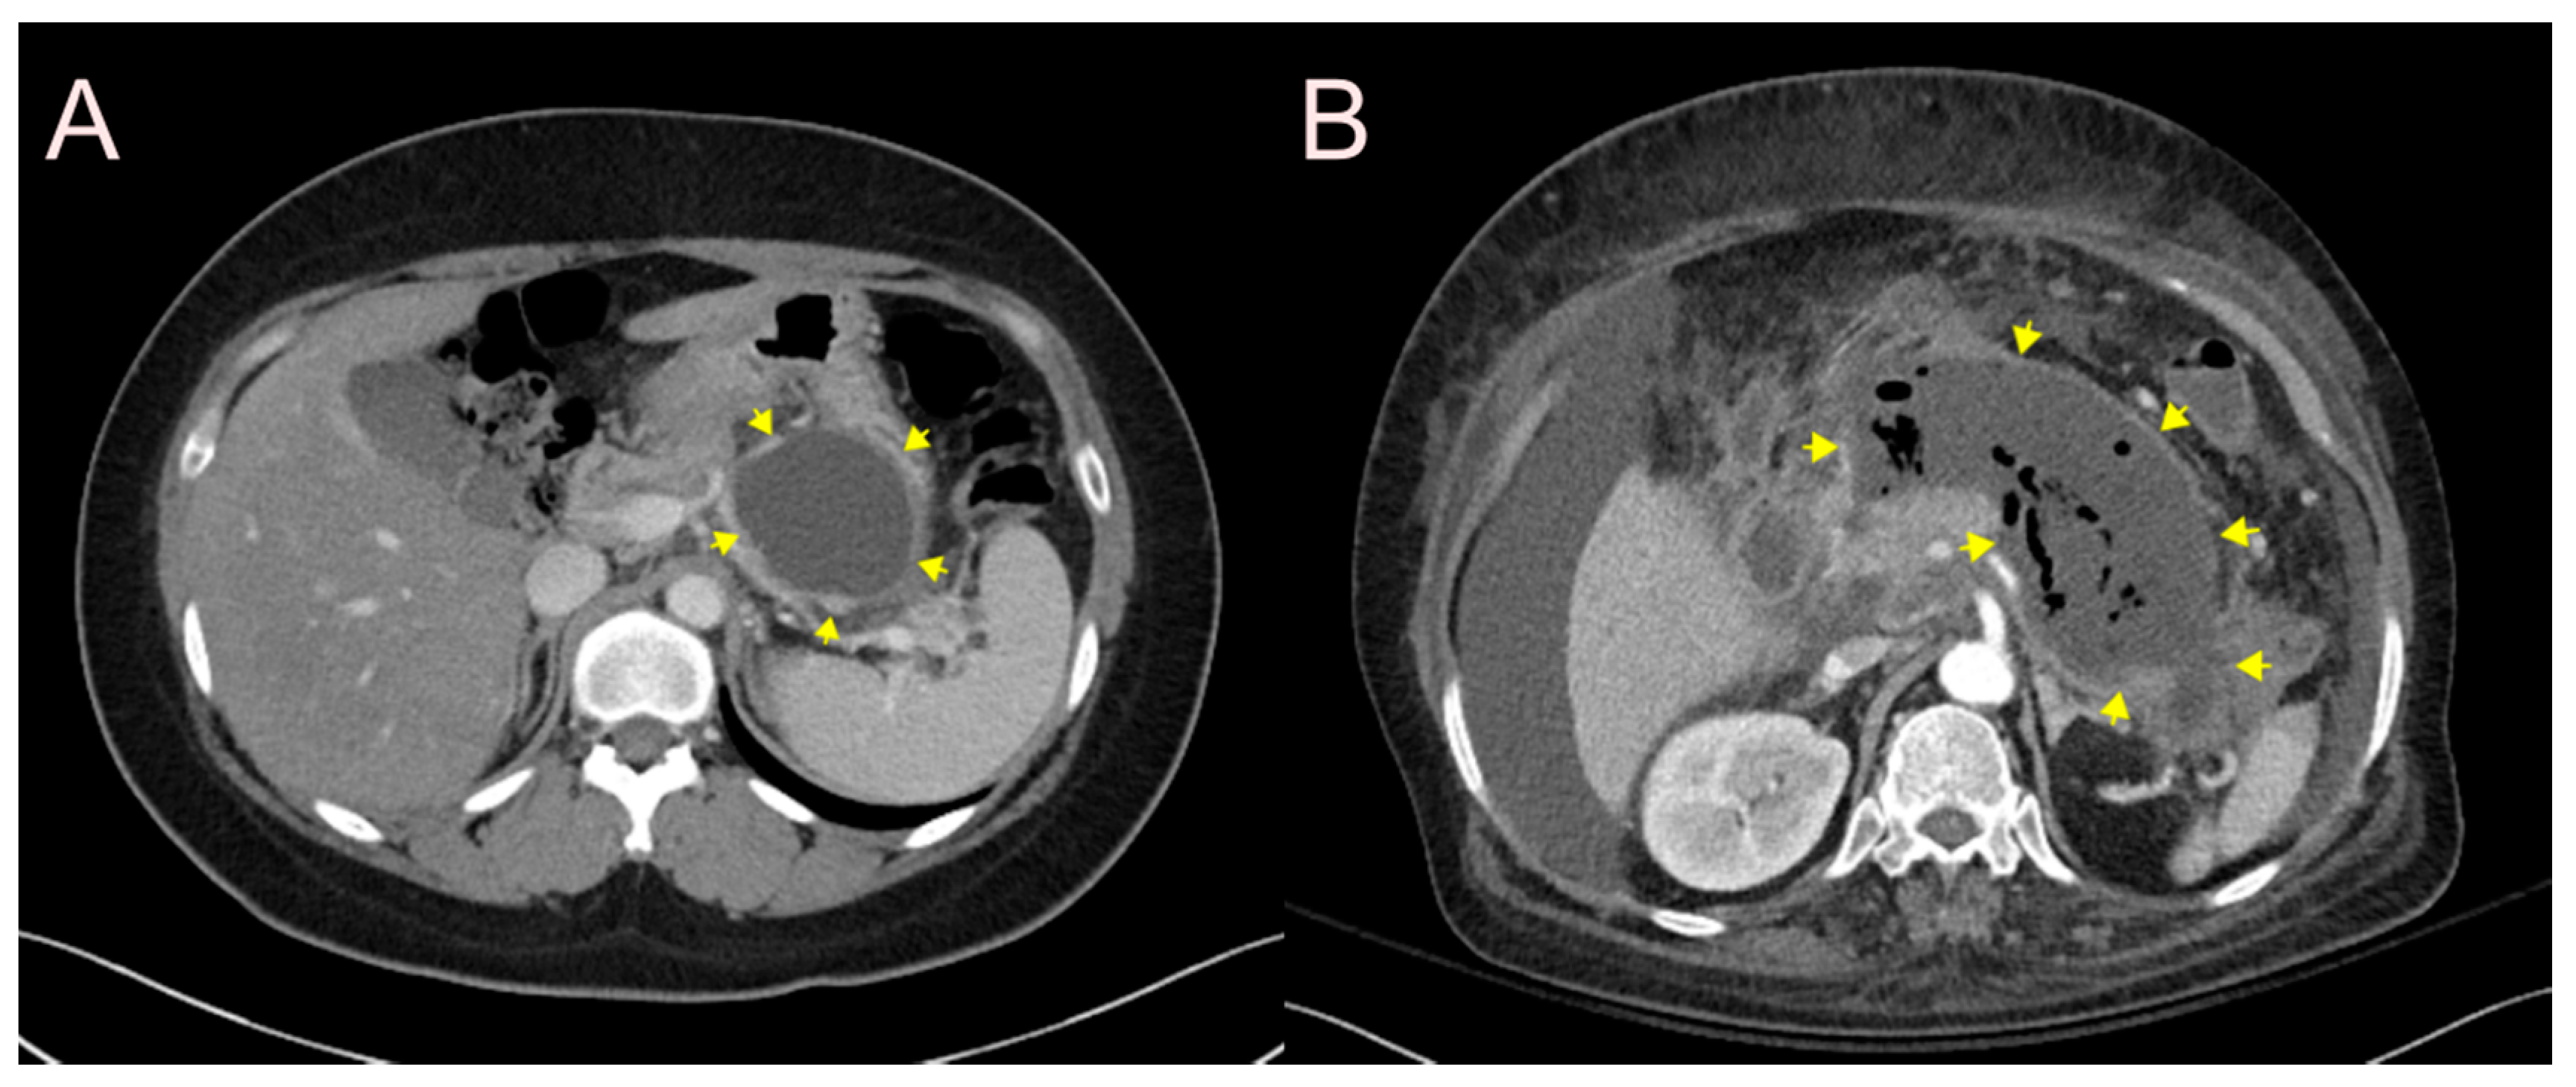

2.1. Stent for EUS-Guided Peripancreatic Fluid Collection (PFC) Drainage